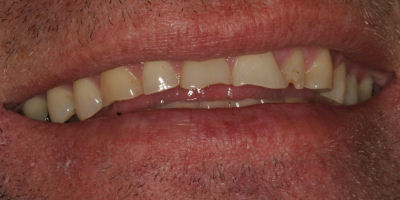

Closing Spaces